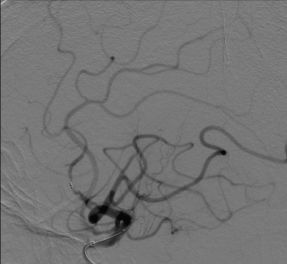

颈内动脉DSA提示颅内存在三处病变血管:大脑中动脉上干闭塞,下干的起始段局部有血栓形成以及一支M2段分支闭塞。

下干取栓后DSA可见下干开通,M2分支以及大脑中动脉上干部分开通。

使用4-20 Solitaire 支架进行MCA上干取栓。 取栓后DSA提示上干完全再通,M2远端分支仍闭塞。